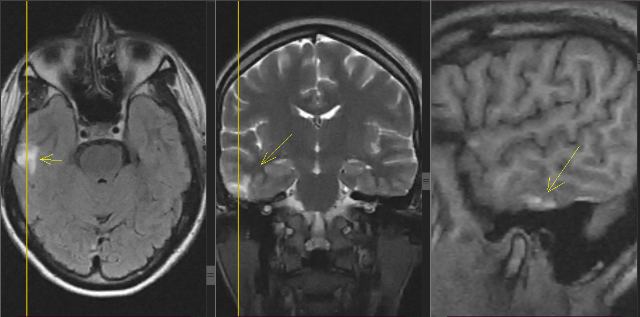

Есть очаги в головном мозге

Есть очаги в головном мозге 114 фото